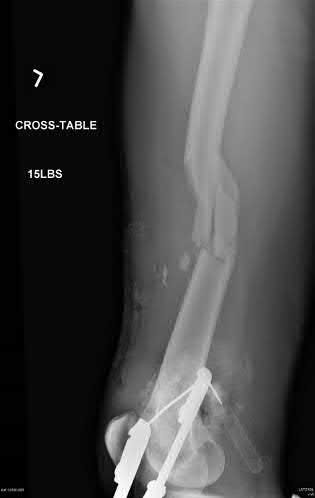

A 15-year-old boy is diagnosed with high-grade intramedullary osteosarcoma of the distal femur.

What is the single most important prognostic factor for his overall survival?

Explanation

In osteosarcoma, the single most important prognostic factor for survival is whether metastatic disease is present at the time of diagnosis. For patients presenting with localized disease, the percentage of tumor necrosis following neoadjuvant chemotherapy (>90% necrosis indicates a good response) becomes the most important prognostic factor.